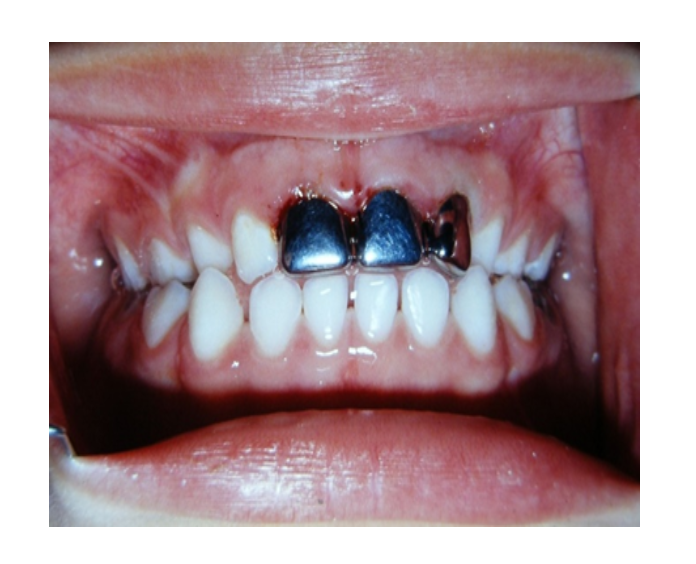

Mordida Cruzada anterior unidental

Mordida Cruzada posterior unilateral

Mordida cruzada posterior bilateral